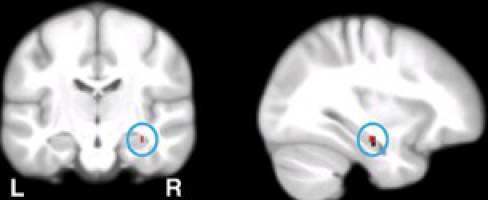

Stress Hormone Reduces Heroin Cravings

Every addiction is characterized by a strong desire for a certain addictive substance, be it nicotine, alcohol or other drug. Researchers at the University of Basel recently conducted a study on heroin addiction and demonstrated that the stress hormone cortisol can reduce addictive cravings. The findings from the research have been published in the medical journal Translational Psychiatry.